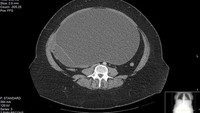

Kista ovarium kanan yang membesar menimbulkan rasa sakit pada bagian tersebut. Biasanya, rasa sakit ini muncul pada awal atau akhir periode menstruasi. (Foto: BMJ Case Reports)